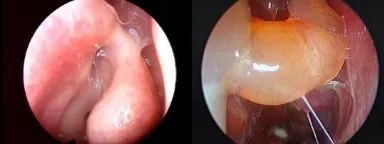

1、内镜检查:来源于中鼻道、嗅裂的黏脓性分泌物,中鼻道粘膜充血、水肿或有鼻息肉。

图1中鼻道息肉

图2 治疗后